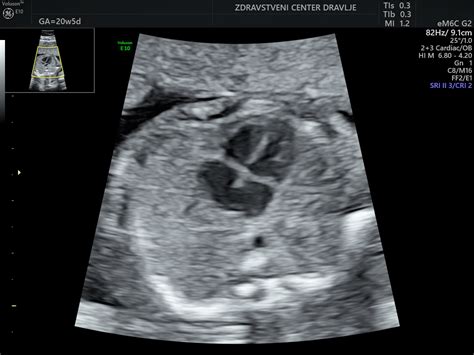

Plod v tem obdobju že meri okoli 12 cm (pri 16 tednih), do 20. tedna pa se začnejo meriti obsegi glavice, trebuha in dolžina stegnenice za oceno telesne teže, ki znaša okoli 300 gramov. Na ultrazvoku so lahko vidni že različni obrazni gibi ploda. Do 24. tedna teža ploda naraste na približno 650 gramov, koža se naguba, nalaga se podkožno maščevje, v pljučih pa se razvijajo pljučni mešički. Posteljica v 24. tednu tehta okoli 200 gramov. V 13. tednu nosečnosti je na pravem mestu tudi že otrokovo črevesje, ki je pripravljeno za prehajanje snovi.

Drugo trimesečje: Običajno vključuje ultrazvočni pregled morfologije ploda v 20. tednu, ki podrobno oceni razvoj otroka. Potrebne so tudi analize krvne slike in urina ter test na nosečnostno sladkorno bolezen med 20. in 24. tednom. Okoli 20. tedna nosečnosti maternica sega do popka.